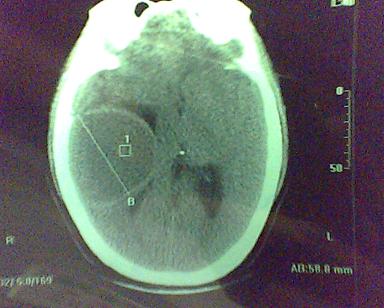

男 31岁 短暂性四肢抽搐 呼叫不应  头胀痛4个多月 无发热 4年前遭棒击头部,当时未到医院检查。余无特殊。病人特穷,未作增强。

这是一个边缘清晰的等密度的囊性占位.密度比较均匀,周围无水肿,我顷向于脑脓肿的可能性大.

右侧乳突蜂房消失,右侧颞叶区囊性占位,水肿不明显,考虑表皮样囊肿或耳源性脑脓肿,+c!。

图象质量太差啦,拜托照好一点,好象从临床症状不太支持脓肿,脑实质内没有水肿,只有轻度战位效应。脓肿壁应再厚点。囊性占位比较合适,建议强化。